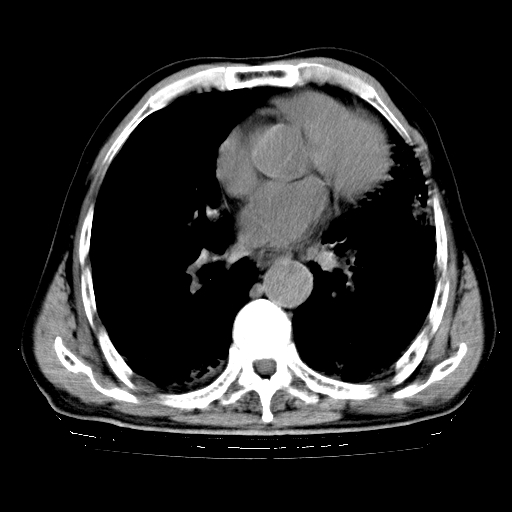

标题: CT25149:男,69岁,反复咳嗽、咳痰五年余,呼吸困难三天。 [打印本页]

男,69岁,反复咳嗽、咳痰五年余,呼吸困难三天。

慢支伴感染、肺气肿、肺心病

慢支伴感染、肺气肿、肺心病!支持!另:间质纤维化!

慢支伴感染、肺气肿、肺心病。双肺间质性改变(间质纤维化)。